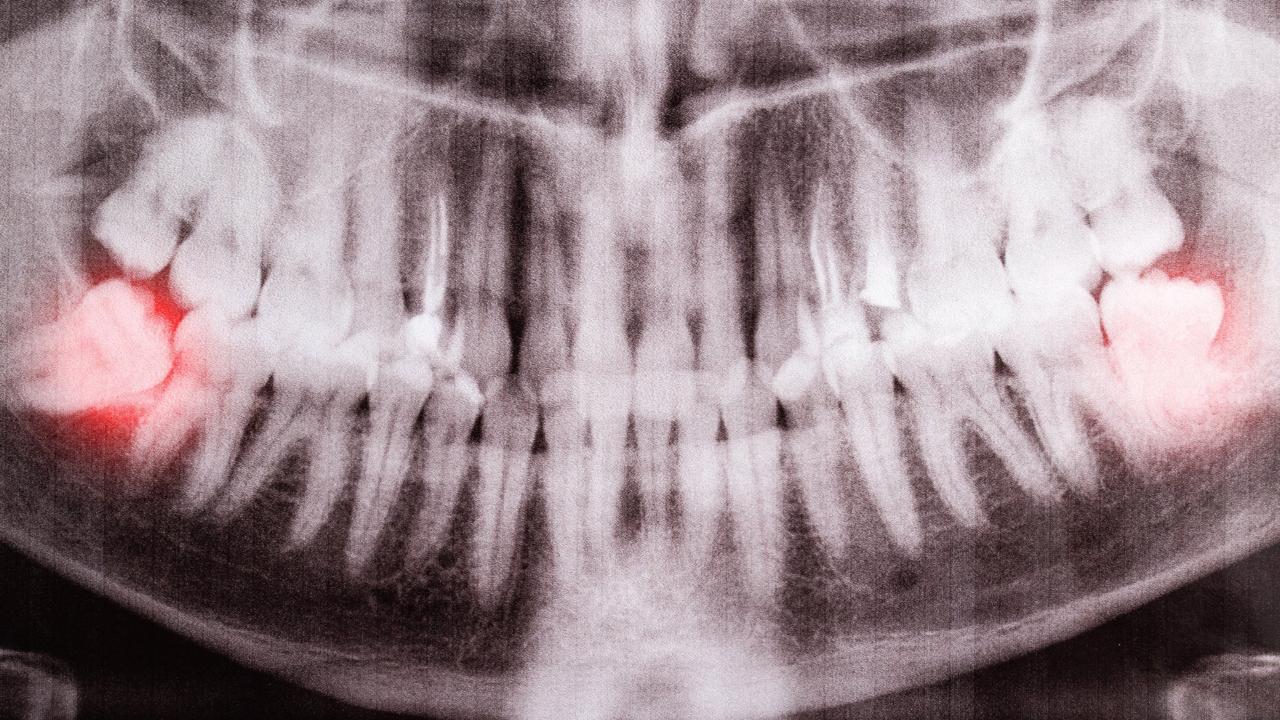

Impaksi berarti gigi gagal tumbuh sempurna karena terhalang oleh gigi lain, gusi, atau tulang rahang. Kadang giginya muncul sebagian (disebut impaksi parsial), kadang tidak muncul sama sekali (impaksi total). Bayangkan gigi bungsu seperti tamu terakhir yang datang ke pesta — tapi kursinya sudah penuh. Akhirnya ia “menyempil” di tempat yang salah, menekan tamu lain, dan menimbulkan kekacauan.

2. Arah tumbuh miring — bisa ke depan, ke belakang, atau ke samping.